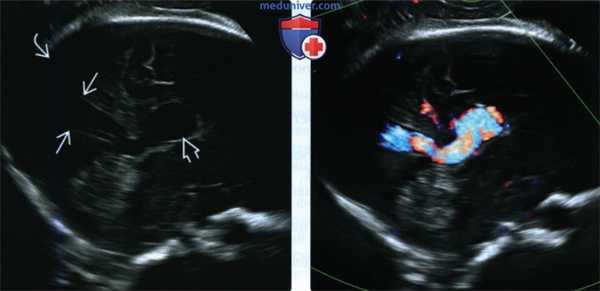

(Слева) В III триместре беременности при ТАУЗИ плода видна внутричерепная «киста». В этом случае подозревали наличие СДУ.

(Справа) При ЦДК видно, что на самом деле «киста» представляет собой сосудистое образование, большая часть которого расположена на покрышке моста, а не в ЗЧЯ. Супратенториальное пространство при УЗИ и МРТ выглядело нормально (внутричерепные артериовенозные фистулы могут стать причиной ишемической энцефаломаляции в результате сосудистого обкрадывания). Обратите внимание на расширенные питающие сосуды виллизиева круга. (Слева) При ЦДК части головки этого же новорожденного в сосудах, питающих артериовенозную фистулу, визуализируется высокоскоростной кровоток с очень низким сопротивлением.